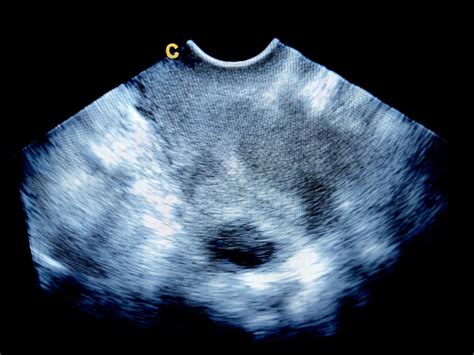

Ginekolog bo pri postavitvi diagnoze upošteval vašo anamnezo, vključno s podatki o zadnji menstruaciji, trajanju krvavitev, uporabi kontracepcije, dojenju in morebitnih drugih zdravstvenih težavah. Pogosto se opravi ginekološki pregled, ultrazvočni pregled maternice in jajčnikov ter po potrebi krvne preiskave (npr. za določitev ravni hormonov, preverjanje krvne slike za oceno anemije zaradi izgube krvi ali preiskave delovanja ščitnice).